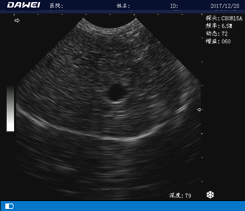

全数字动物超声诊断仪

采用多波束数字成像技术图像更清晰

·中小动物的肝、胆,脾、肾、膀胱、子宫、妊娠等各组织器官的检查和病变的诊断

·牛、羊、马、猪等大动物的孕检和背膘厚度测定